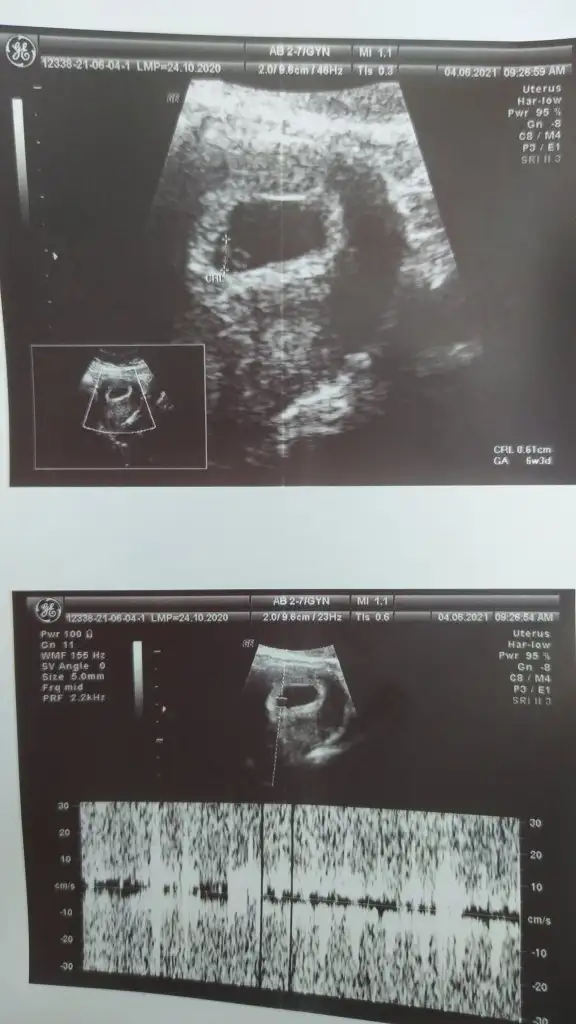

dualarım herşey yolunda dedi haftası ile uyumlu dedi 6+3 çıktı ultrosonda da şükür

kaç mm olmuş minnoş? Ultrason görüntüsünü atar mısın?Kızlar çok şükür duyduk klap atışını minnoşumun yaanasıl güçlü atıyor güp güp diye

Rabbim ne kadar büyük ya hikmetinden sual olunmaz şuncacık şey kalbi atıyor can oluyor